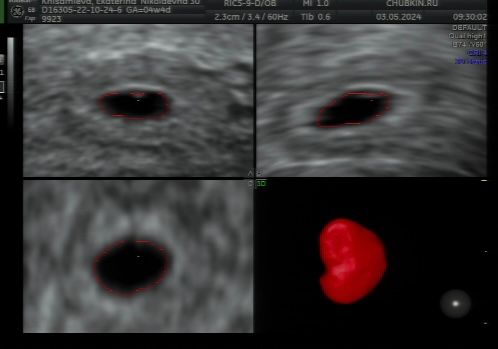

Сходили на первое узи ❤️👶, 14 дпп. ХГЧ на 13 дпп 1473

поздравляю с первыми фотками) теперь растите в срок, развивайтесь и получайте только самые лучшие эмоции от беременности